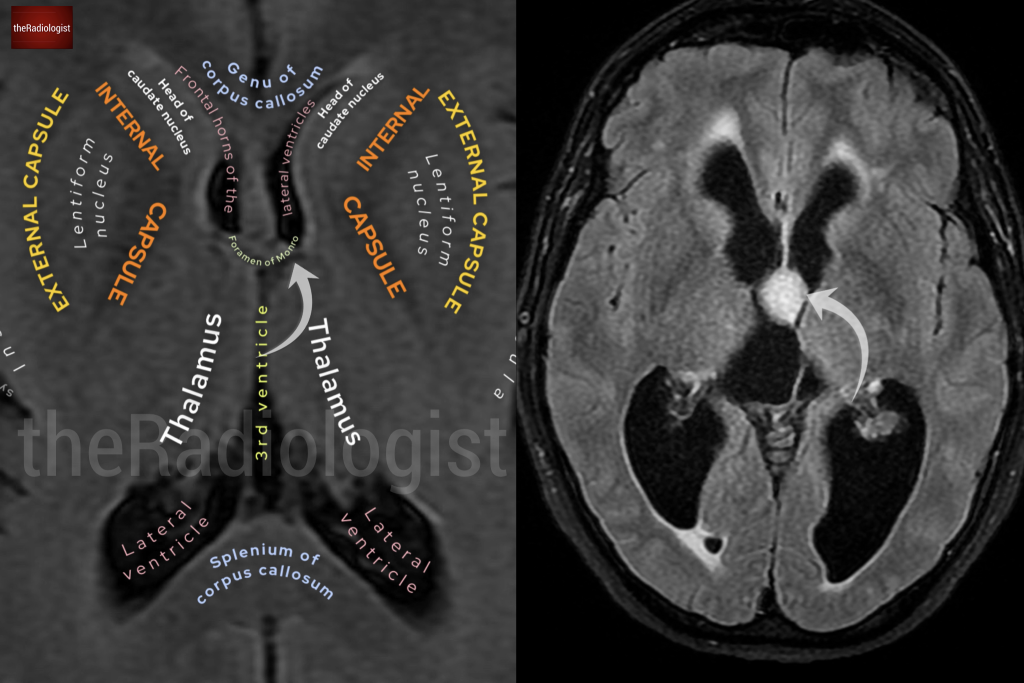

Have a look at the normal annotated brain scan below and compare it to our case.

A normal brain scan shows that the foramen of Monro connects the lateral ventricles to the third ventricle. However, in our patient’s scan, there is a well-defined lesion in the roof and anterior aspect of the third ventricle, right at the foramen of Monro.

Note the normal anatomy of the foramen of Monro on the left and the presence of an obstructing lesion on the image on the right.